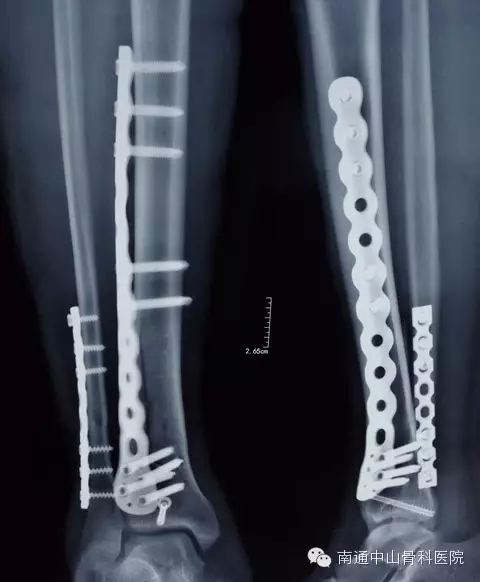

1月11日上午8:30在腰硬联合下,由李龙付主任亲自为患者行“右胫腓骨中下段粉碎性骨折切开复位钢板螺丝钉内固定术”。术中复位腓骨后外侧置入钢板一块、螺丝6枚固定,复位胫骨后外侧置入锁定钢板一块、螺丝钉9枚,胫骨远端置入空心螺丝钉1枚,术中透视见骨折复位满意。手术整个过程紧张而有序,2个小时后手术结束。

术后照片